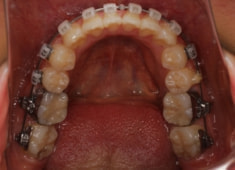

治療前

治療開始時